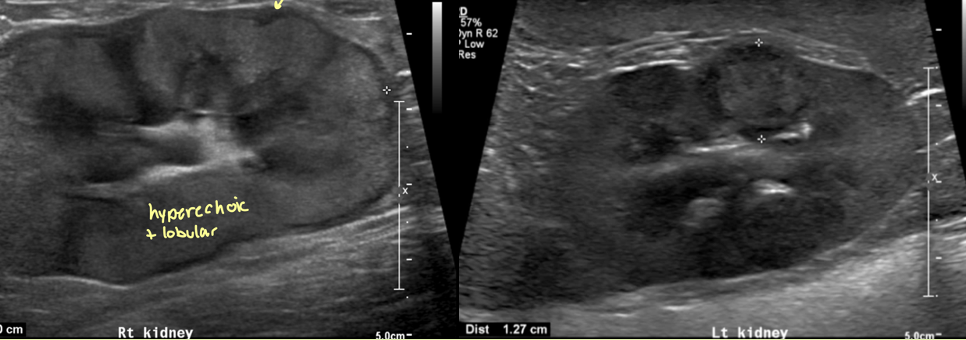

6 reasons for Diffuse increase in cortical echogenicity kidneys

Normal in cats – fat deposition in the tubules

inflam disease - glomerulonephritis, interstitial nephritis

End-stage renal disease – kidneys also small and irregular

Toxic - ethylene glycol tox

Renal dysplasia – kidneys also small and irregular

Neoplasia

what are the 3 ways to describe CM junction distinction

retained - both equally bright

enhanced - medulla normal, cortex bright

decreased -medulla also bright

2 reasons for decreased CM junction distinction

chronic renal disease

renal dysplasia